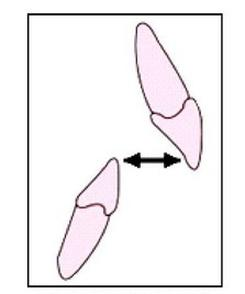

Odległość brzegu siecznego siekacza górnego od powierzchni wargowej siekacza dolnego zaznaczona na rysunku strzałkami określa się nazwą

A. openjet.

B. overjet.

C. openbite.

D. overbite.